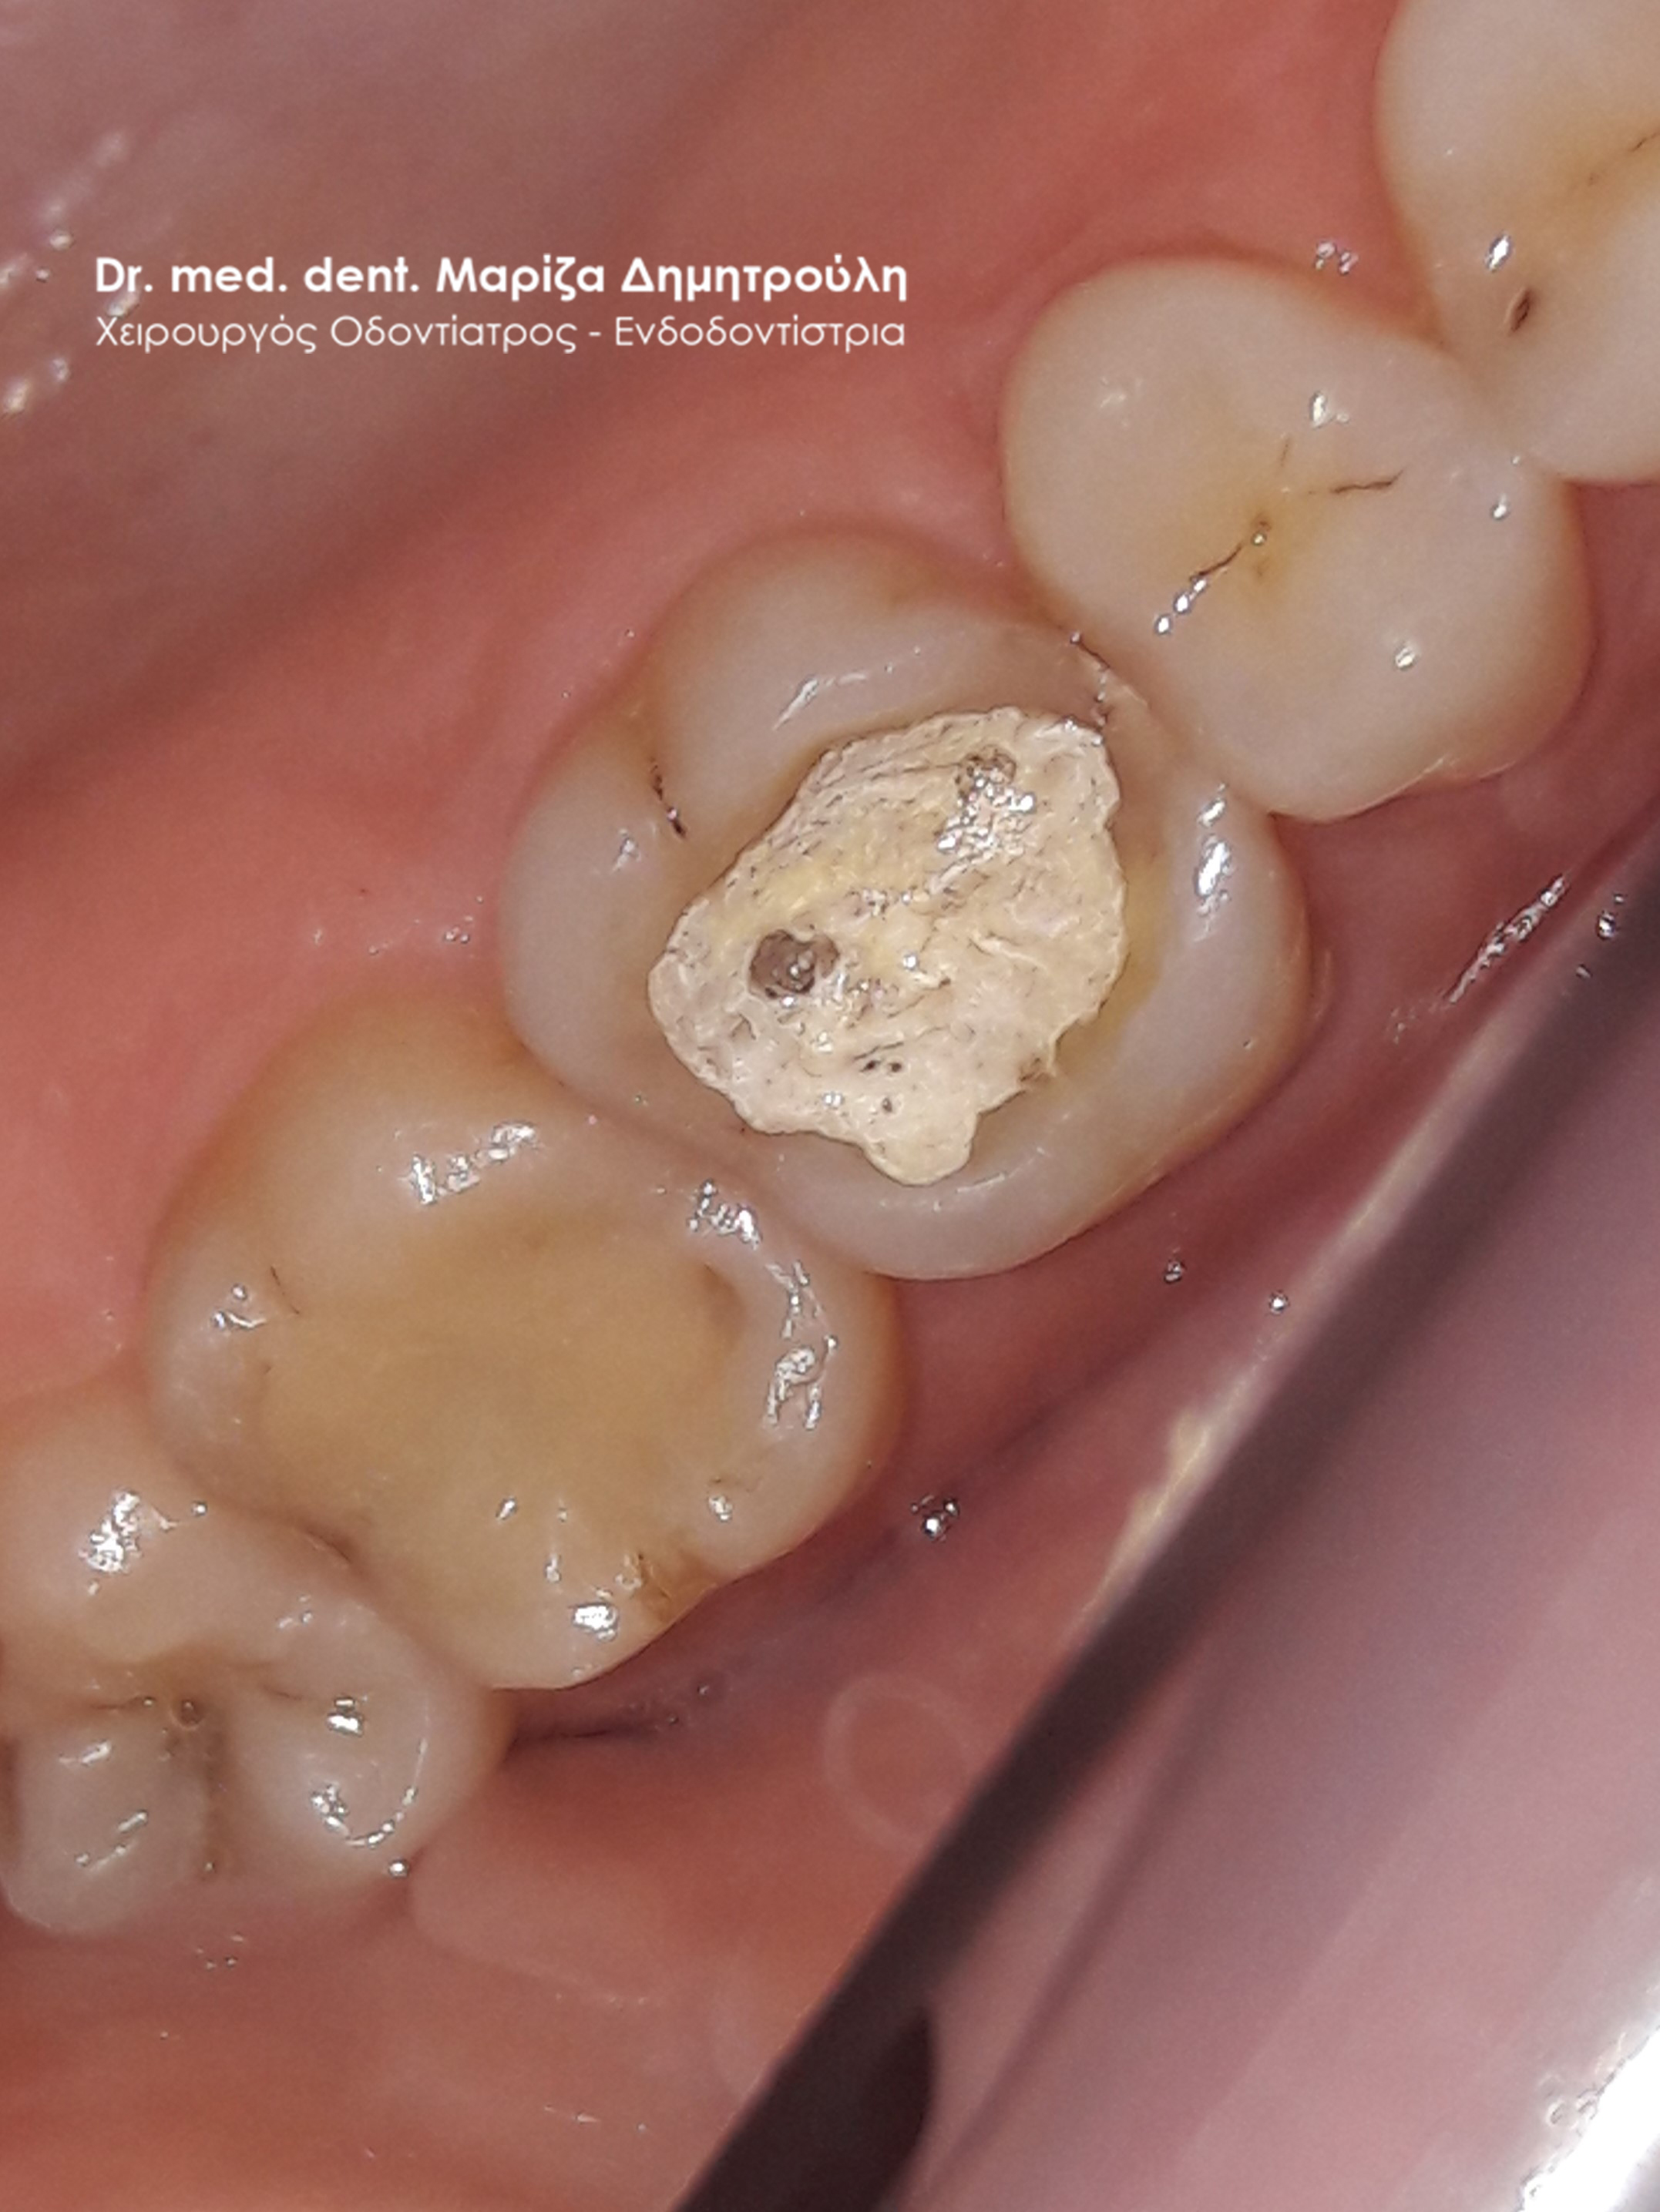

Η ασθενής επισκέφτηκε το ιατρείο καθώς ο πρώτος κάτω δεξιός γομφίος την πονούσε περιοδικά. Μετά την κλινική εξέταση διαπιστώθηκε ένα παλιό μεγάλο σφράγισμα αμαλγάματος, του οποίου τα όρια δεν είχαν επαφή με το δόντι και είχαν δημιουργηθεί κενά μεταξύ του μαύρου σφραγίσματος και οδοντικών τοιχωμάτων. Αποφασίστηκε η αντικατάσταση του παλιού σφραγίσματος με νέο λευκό σφράγισμα σύνθετης ρητίνης.

Η μεσαία φωτογραφία δείχνει την το έλλειμμα του δοντιού μετά την αφαίρεση του σφραγίσματος αμαλγάματος και των τερηδονισμένων οδοντικών ιστών. Στη δεξιά φωτογραφία φαίνεται η τελική αποκατάσταση του δοντιού.

ΠΡΙΝ

Εικόνα του δοντιού μετά την αφαίρεση του παλιού σφραγίσματος και της τερηδόνας

META